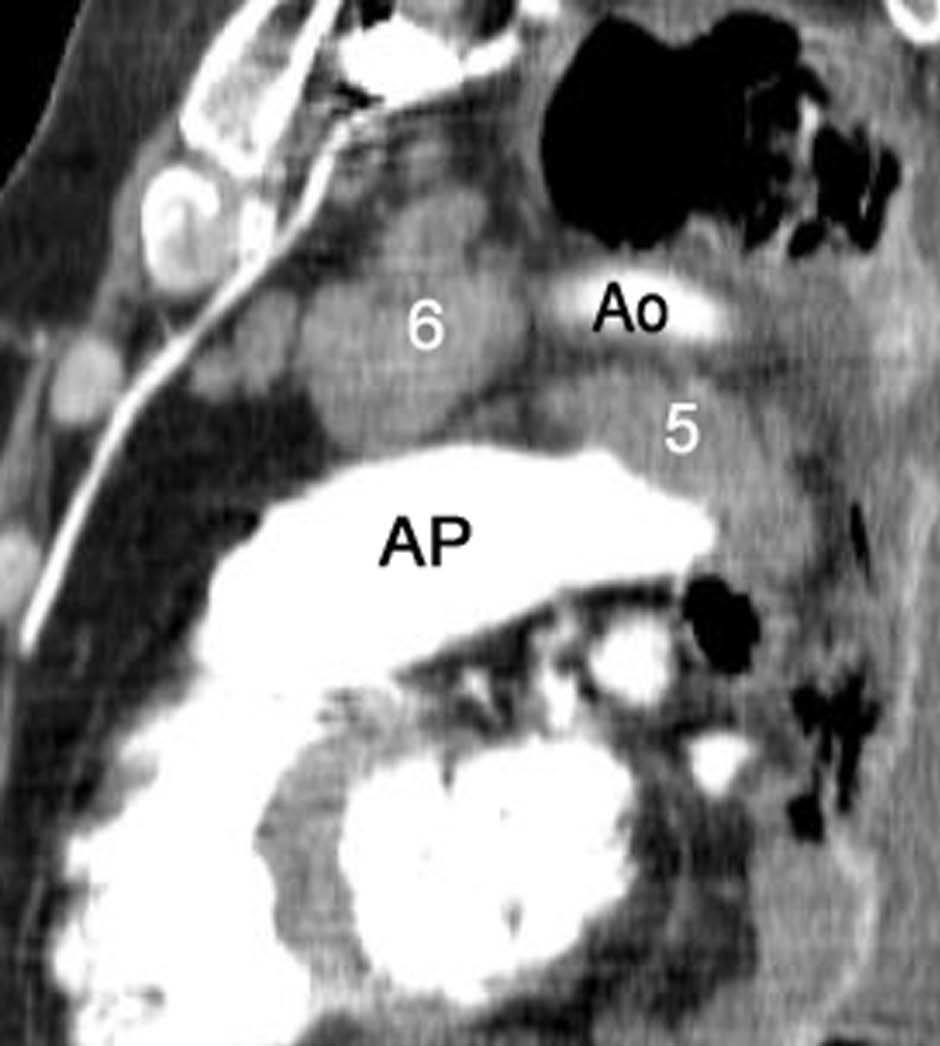

Fig. 11.--N2. (A) Corte axial de tomografía computarizada (TC) con contraste. Nódulo heterogéneo en el segmento 6 del lóbulo inferior derecho con infiltración de la vena pulmonar inferior (flecha). (B) En la reconstrucción de volumen se ponen de manifiesto la infiltración tumoral de la vena pulmonar (flecha negra), la adenopatía hiliar (asterisco) y una adenopatía calcificada lobar superior derecha (flecha blanca).

Fig. 12.--Estaciones ganglionares para la estadificación del cáncer de pulmón. Las reconstrucciones multiplanares (MPR) son de gran ayuda para precisar los territorios ganglionares afectos. Correlación de los territorios ganglionares entre el mapa ganglionar de Mountain y Dressler y una reconstrucción coronal de un paciente con afectación adenopática mediastínica e hiliar bilateral. (A y B) Ganglios mediastínicos superiores e inferiores e hiliares. (C y D) Ganglios aórticos. AP: arteria pulmonar. Ao: aorta.

La precisión de la TC para predecir la afectación ganglionar mediastínica, pese a la ayuda que suponen las reconstrucciones MPR y 3D en la valoración de determinados territorios ganglionares (espacio subcarinal, hilio o ventana aortopulmonar) (fig. 11), sigue teniendo muchas limitaciones. El único criterio que se emplea para considerar que un ganglio es patológico es el tamaño (cuando el eje corto es mayor de 10 mm, salvo en el espacio subcarinal que se acepta hasta 12 mm). El empleo únicamente de criterios de tamaño hace que la TC sea una técnica poco precisa en la valoración de la afectación ganglionar. En un metaanálisis reciente13 la sensibilidad global de la TC para estadificar el mediastino fue de un 57%, con una especificidad del 82%, un valor predictivo positivo (VPP) del 56% y un valor predictivo negativo (VPN) del 83%. Lo que es innegable es la capacidad de la TC para mostrar un mapa de los ganglios tanto hiliares como mediastínicos (fig. 12), lo cual es de gran utilidad en la determinación del factor N. La valoración del territorio hiliar puede ser compleja por la agrupación de estructuras vasculares, por lo que además de la opacificación adecuada de éstas, es de utilidad la identificación de la pérdida del ángulo de la bifurcación (carina secundaria), ya que el eje corto significativo en este territorio es de 3 mm. Como ya hemos comentado, también es de gran ayuda en esta localización el empleo de reconstrucciones (fig. 11)5.